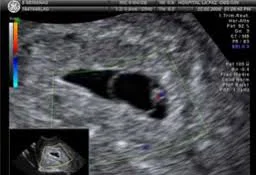

El embrión mide alrededor de 1.6 cm. Las extremidades ya muestran los esbozos de los dedos. La cola embrionaria comienza a desaparecer, y los ojos y oídos siguen su desarrollo. El cerebro sigue creciendo rápidamente, y la frecuencia cardíaca del embrión es detectable por ecografía. A esta etapa, los principales órganos están formados.

El feto mide unos 6 cm y pesa alrededor de 14 gramos. Los riñones empiezan a producir orina, que se expulsa en el líquido amniótico. Los genitales externos están lo suficientemente formados para determinar el sexo mediante una ecografía. El sistema nervioso continúa desarrollándose, permitiendo movimientos más coordinados.